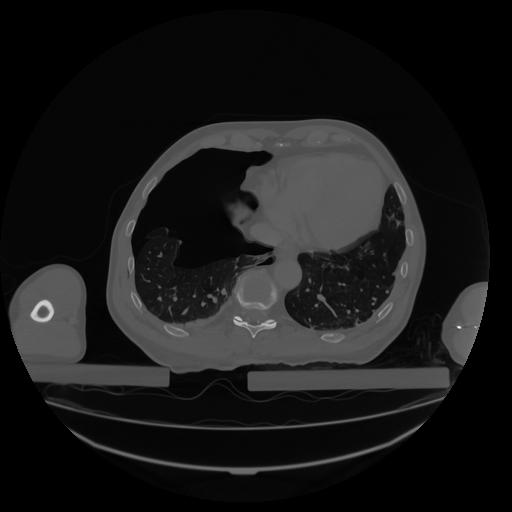

34 CUERPO,CE,Vol,1.0,CUERPO,,